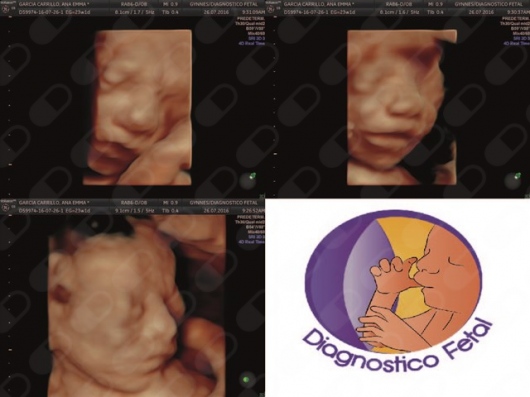

Diagnostico Fetal - Gynnes

• Consultorio privado Ultrasonido 3D  •